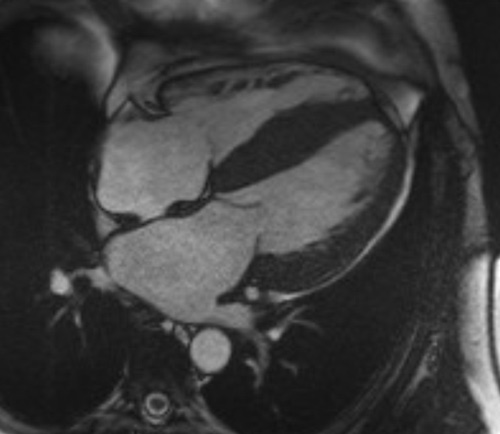

On retrouve généralement une hypertrophie VG diffuse, concentrique, une hypertrophie du VD, une dilatation biatriale, une infiltration des oreillettes, du septum inter-atrial et des feuillets valvulaires. Elle permet de quantifier précisément une dysfonction systolique ventriculaire gauche et droite éventuelle associée. Un épanchement péricardique et/ou pleural peut être également retrouvé, surtout en cas d’amylose cardiaque AL (Figure 5).

Figure 5 : Evaluation morphologique en IRM cardiaque en cas d’amylose cardiaque

5a : Patient avec amylose cardiaque TTR : hypertrophie VG diffuse, hypertrophie du SIA, dilatation biatriale

5b : Patient avec amylose cardiaque AL : hypertrophie biventriculaire, hypertrophie du SIA, dilatation bi atriale et épanchements péricardique et pleuraux